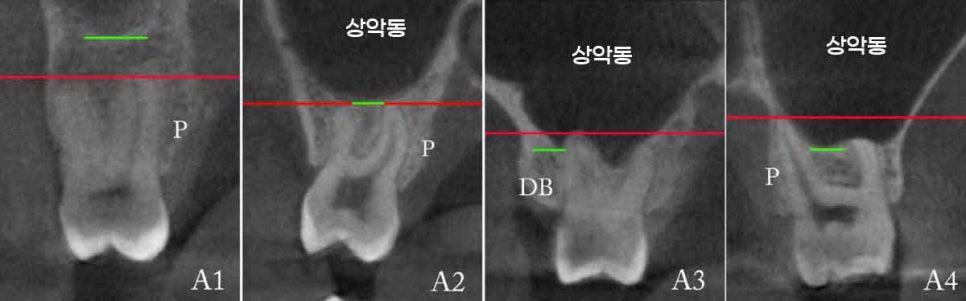

우선 엑스레이(X-ray) 상으로는,

이식된 골이 상악동저를 따라 매끄럽고 둥근 형태의

‘동산 모양’(dome shape)으로 형성되어 있는지를 확인합니다.

이 모양이 불규칙하거나 일부가 꺼져 있다면,

상악동막 손상 또는 이식재 흡수 가능성을 의심해 볼 수 있죠.